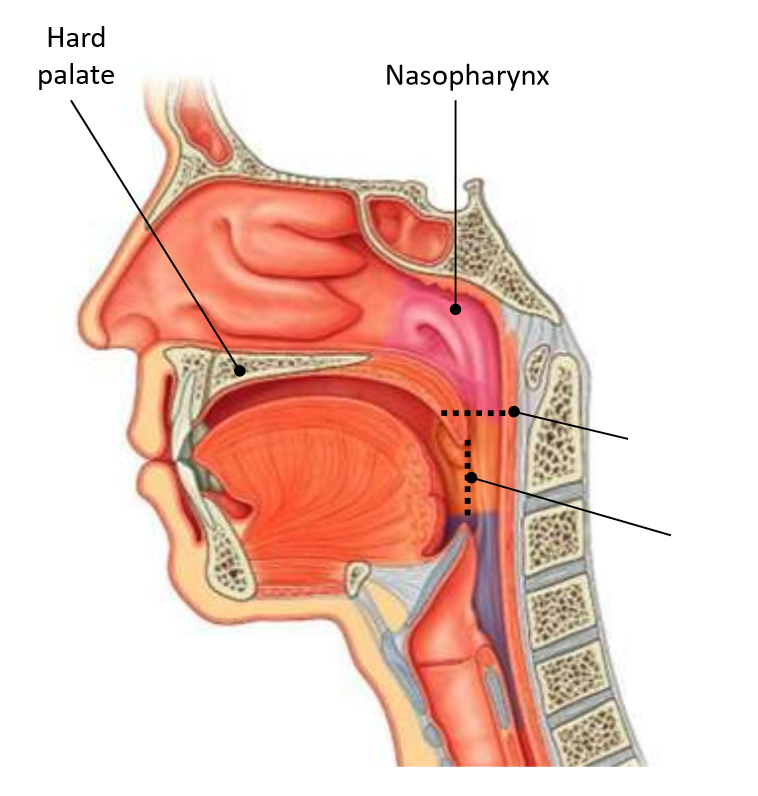

Which area of the head and neck do 1, 2, and 3 make?

pharynx

What region is 1?

nasopharynx

What region is 2?

oropharynx

What region is 3?

laryngopharynx

What is the horizontal dotted line?

pharyngeal isthmus

What is the vertical dotted line?

oropharyngeal isthmus